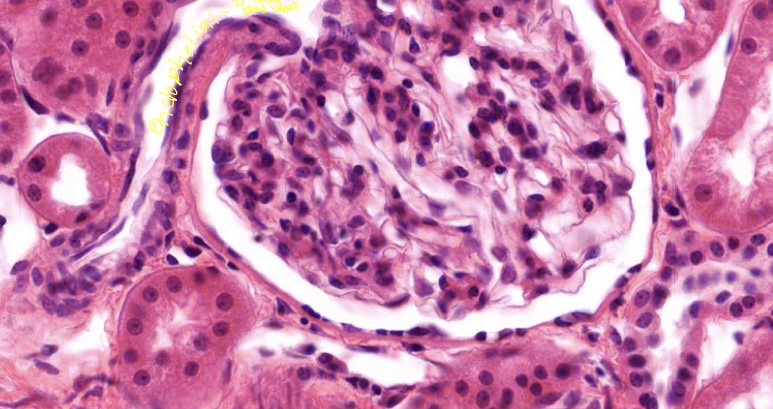

term image

Simple squamous in bowman capsule kidney

Kidney epithelium is derived from

Mesoderm